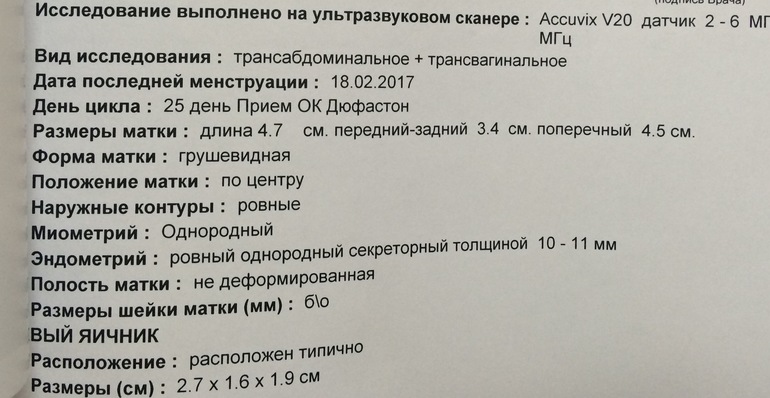

Девчата ,а вот и я с результатами узи!!немного в шоке )))в прошлый цикл через 5 дней после овуляции жт уже почти не видно было и эндик уменьшился .Сейчас я ходила не к своей узистке в другую больницу (но она не из дешёвых ).В общем эндик 10 -11 (сразу после овули он был 11) и жт 25!!(а было 20-21 после овуляции )Сегодня 8 дпо и что думаете на этот счёт?все-таки шанс есть??